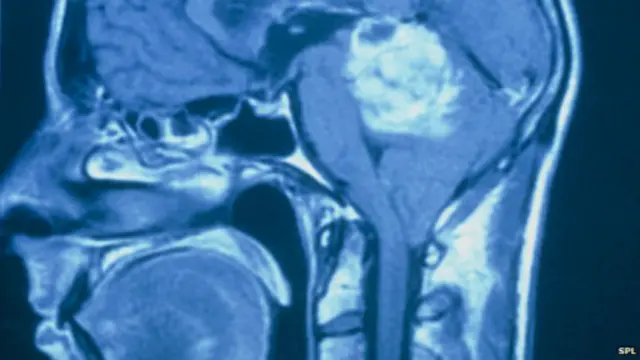

Enstitü'deki araştırma ekibi, beyinde yayılma eğilimi gösteren ve glioblastoma adı verilen tedavisi güç beyin tümörleri üzerinde çalışma yapıyordu.

Ölümcül beyin tümörleri